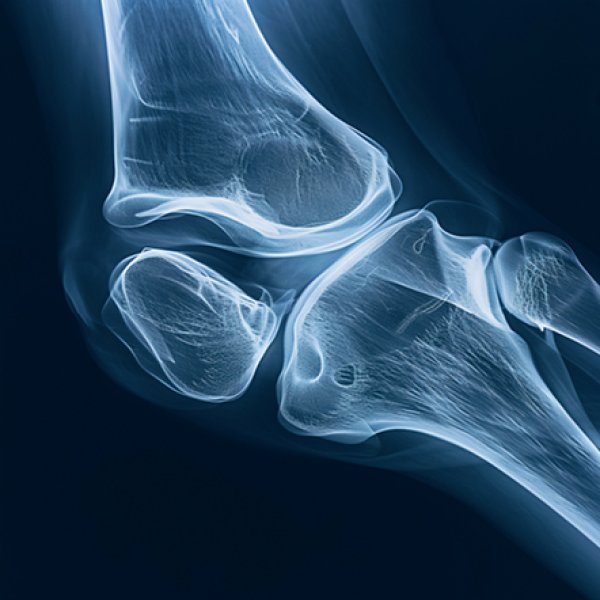

raio x joelho

Este encontro, realizado na SRNOM - Seção Regional Norte da Ordem dos Médicos, reúne especialistas para discutir os principais desafios no diagnóstico, tratamento e reabilitação de condições do joelho. O evento aborda tópicos desde instabilidade ligamentar e artroplastia em casos complexos até avanços em reabilitação e controlo da dor pós-cirúrgica, promovendo a partilha de conhecimentos e técnicas inovadoras na área.

Tem como principais objetivos explorar estratégias modernas para reconstruções ligamentares multiligamentares; debater soluções para artroplastia primária em joelhos complexos, infeções peri-protésicas e revisões complexas; apresentar avanços no tratamento de instabilidade patelofemoral, incluindo displasia troclear e técnicas combinadas; e discutir inovações na reabilitação pós-cirúrgica, controlo da dor crónica e métodos de recuperação acelerada.